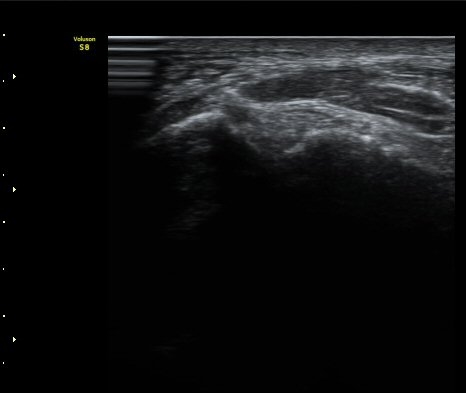

ÃÊÀ½ÆÄ Åõ½ÃÇÏ ºÎÇϰ˻翡¼­ ºñ°ñ°ú ÀδëºÎÂøºÎ¿Í  ºñ°ñ°ú °Å°ñ»çÀ̰¡ ¹ú¾îÁöÁö ¾Ê´Â´Ù

(樨毢 2).